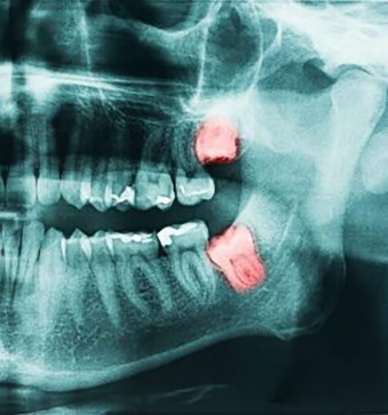

Gömülü yirmi yaş dişleri alt ve üst çenelerde ağızın en gerisinde bulunan ve yer darlığından dolayı normal süremeyen veya gelişemeyen dişlerdir.

Yirmi yaş dişleri genellikle 17-25 yaşları arasında bir zamanda sürerler. Bazı hastalarda yirmi yaş dişleri herhangi bir problem yaratmadan sürerek ikinci molar dişin hemen arkasında yerlerini alırlar. Ama çoğu vakada ağızda üçüncü molar dişlerin sürmesi için gerekli alan bulunmamaktadır. Bu yer darlığından dolayı yirmi yaş dişleri gömük kalabilir. Gömülü yirmi yaş dişleri kısmi olarak sürmüş olabilecekleri gibi tamamıyla da gömük olabilir

- Kistler: Yirmi yaş dişleri çene kemiği içerisinde bir kese içerisinde gelişir .Bu kese sıvı ile dolarak çene kemiğine zarar veren bir kiste neden olabilir. Çok nadir durumlarda iyi huylu tümörlere dönüşebilir.